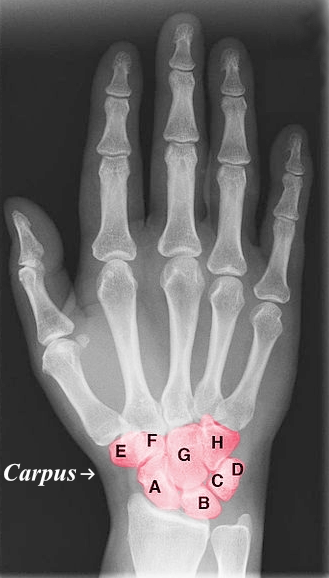

Purple Area

Carpus

Green Area

Metacarpal

Blue Area

Proximal Phalanges Digits 1-5

Yellow Area

Middle Phalanges Digits 2-5

Red Area

Distal Phalanges Digits 1-5